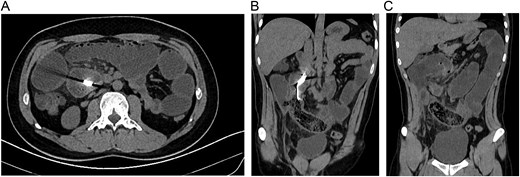

Leucocytosis, with neutrophilia, along with an elevated C-reactive protein, was noticed, and due to his clinical findings, an acute abdomen due to adhesions was suspected. Therefore, an abdominal computed tomography (CT) was requested to have a surgical plan. To the surprise of the medical team, the CT unveiled severe dilation of loops of the small bowel and an intraluminal foreign body with tiny air bubbles containing a metallic marker suggestive of an intraluminal gossypiboma (Fig. 1A–C).

(A) CT, dilation of small bowel loops is seen with obstruction and a hyperdense image in the bowel. (B) CT, reveals a spongiform pattern of mixed mass with gas bubbles inside the intestine. (C) CT, reveals a spongiform pattern with dilated bowel.